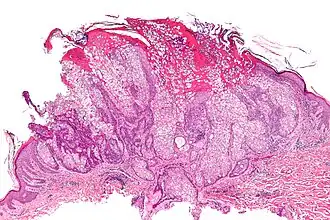

- d'atteintes dermatologiques : lésions à type d’adénome sébacé, de kératoacanthome, de carcinome ou d'épithélioma sébacé ;